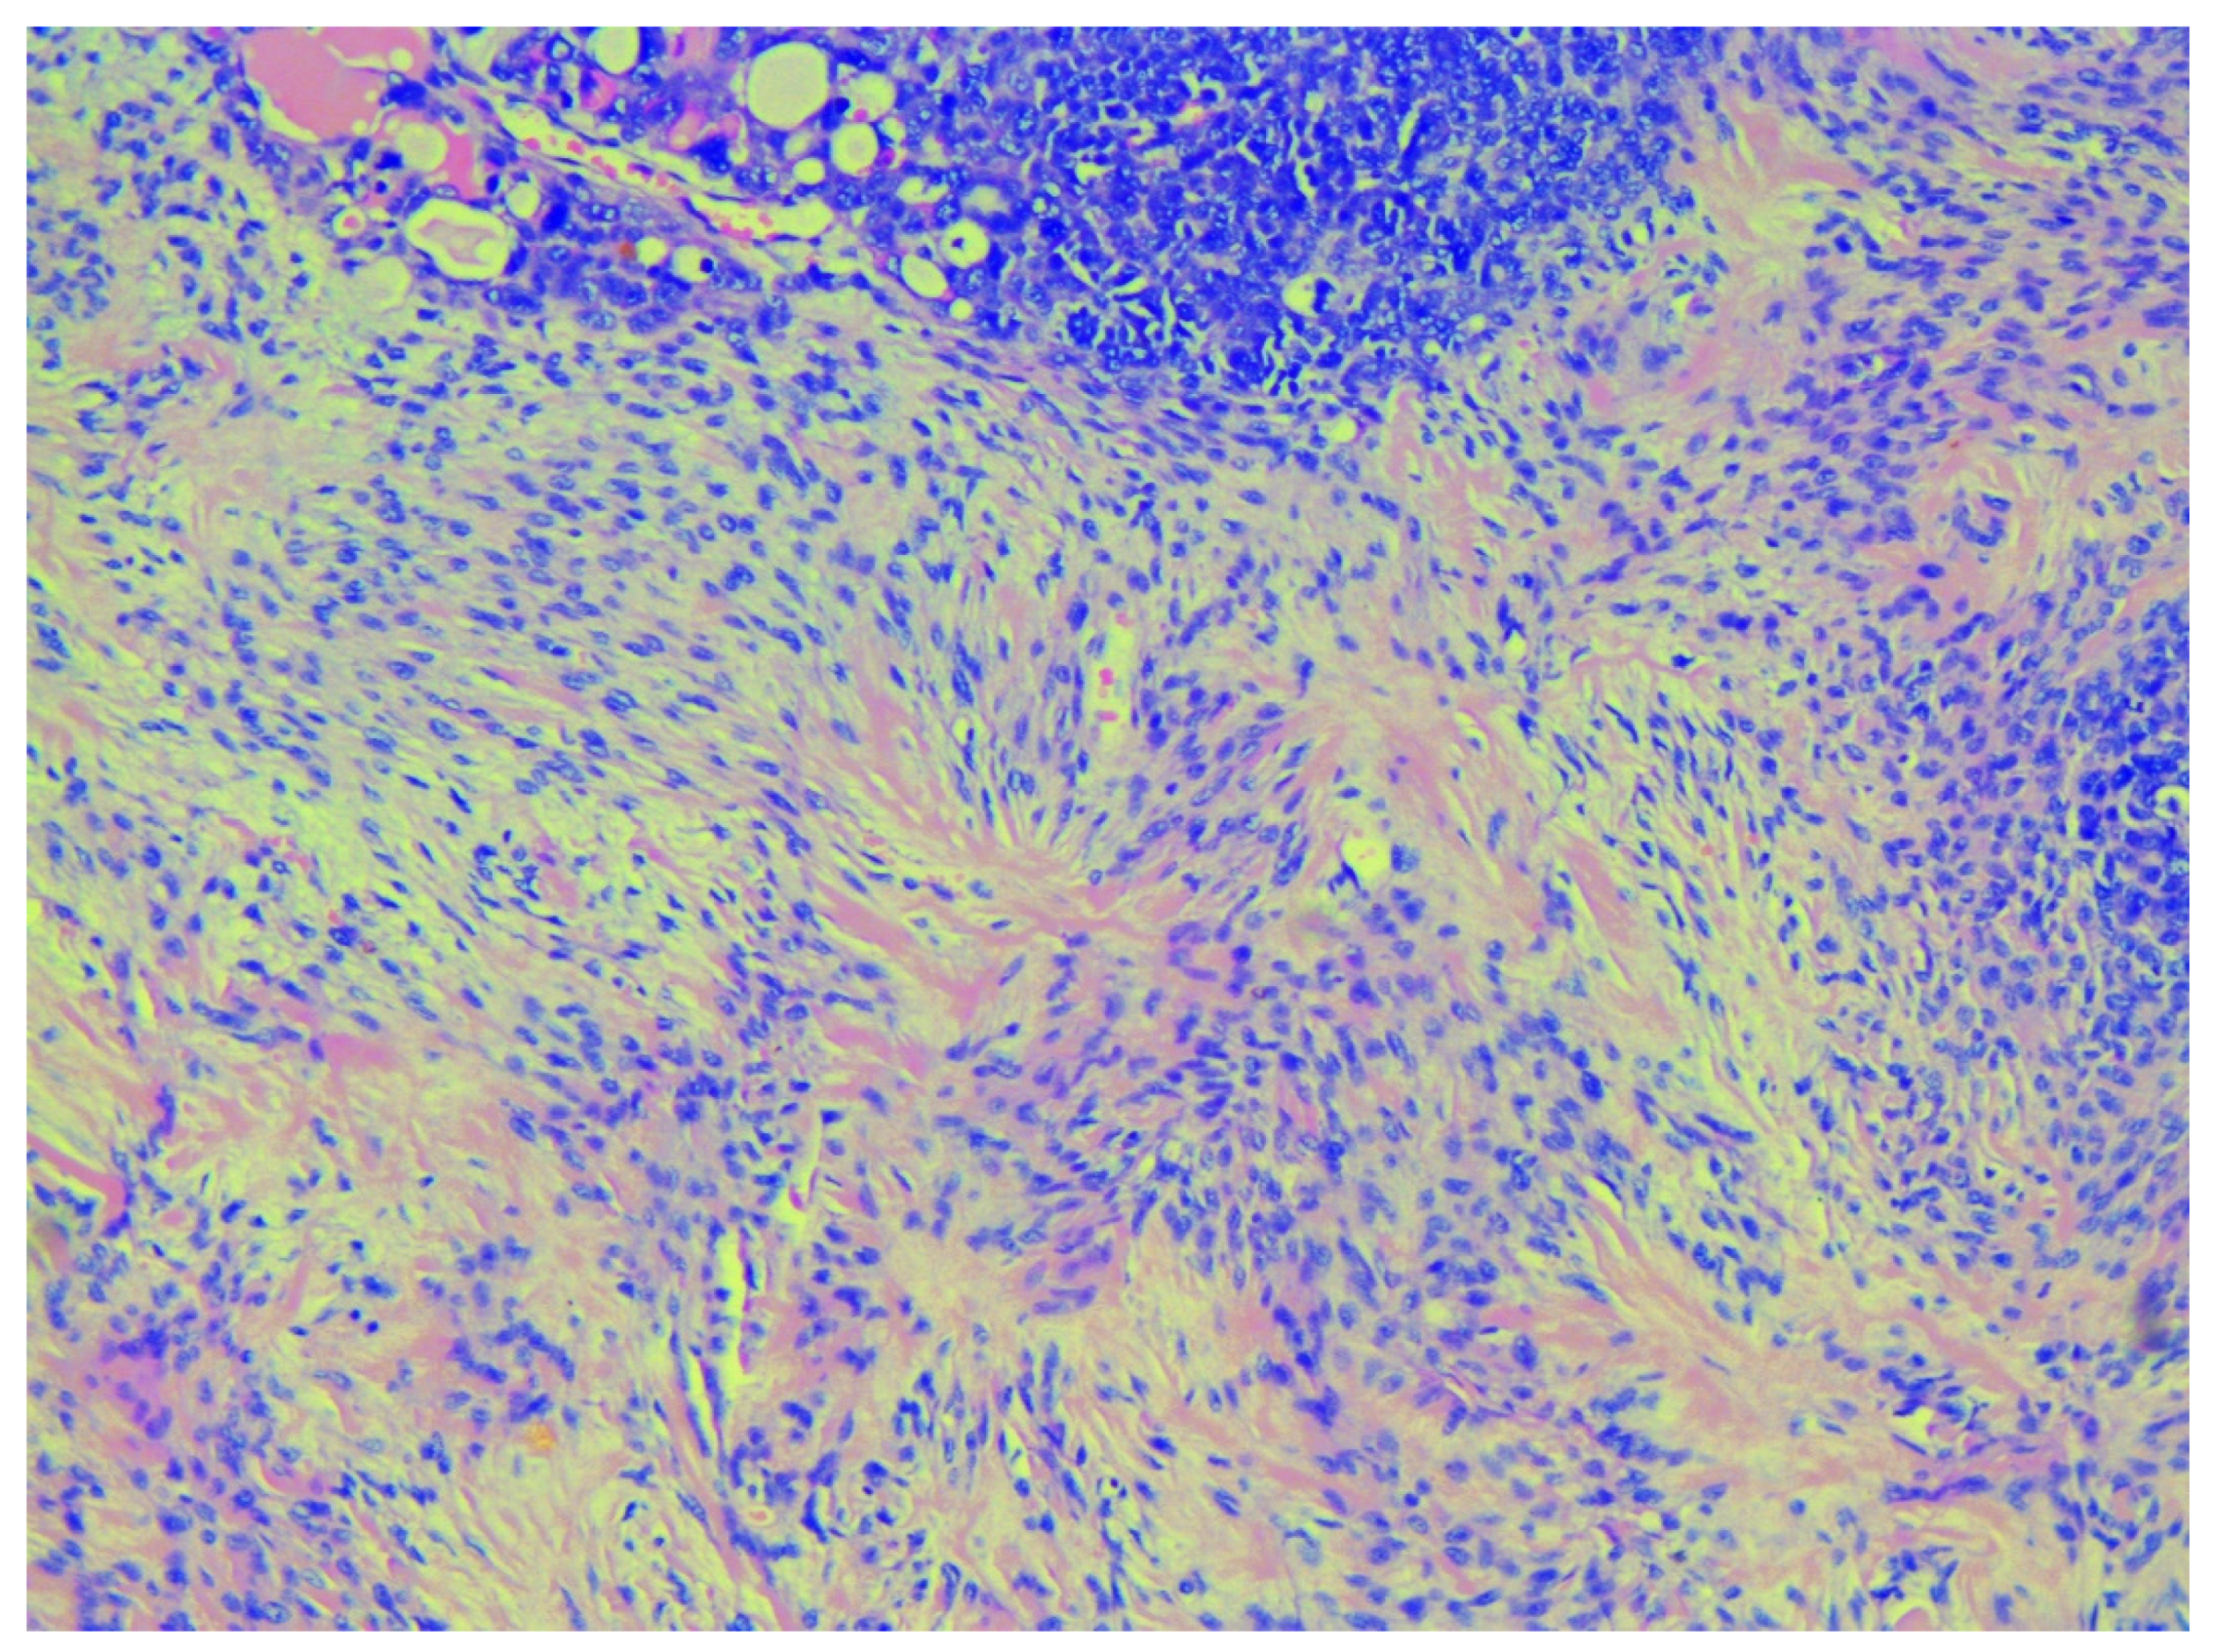

2. Case Report